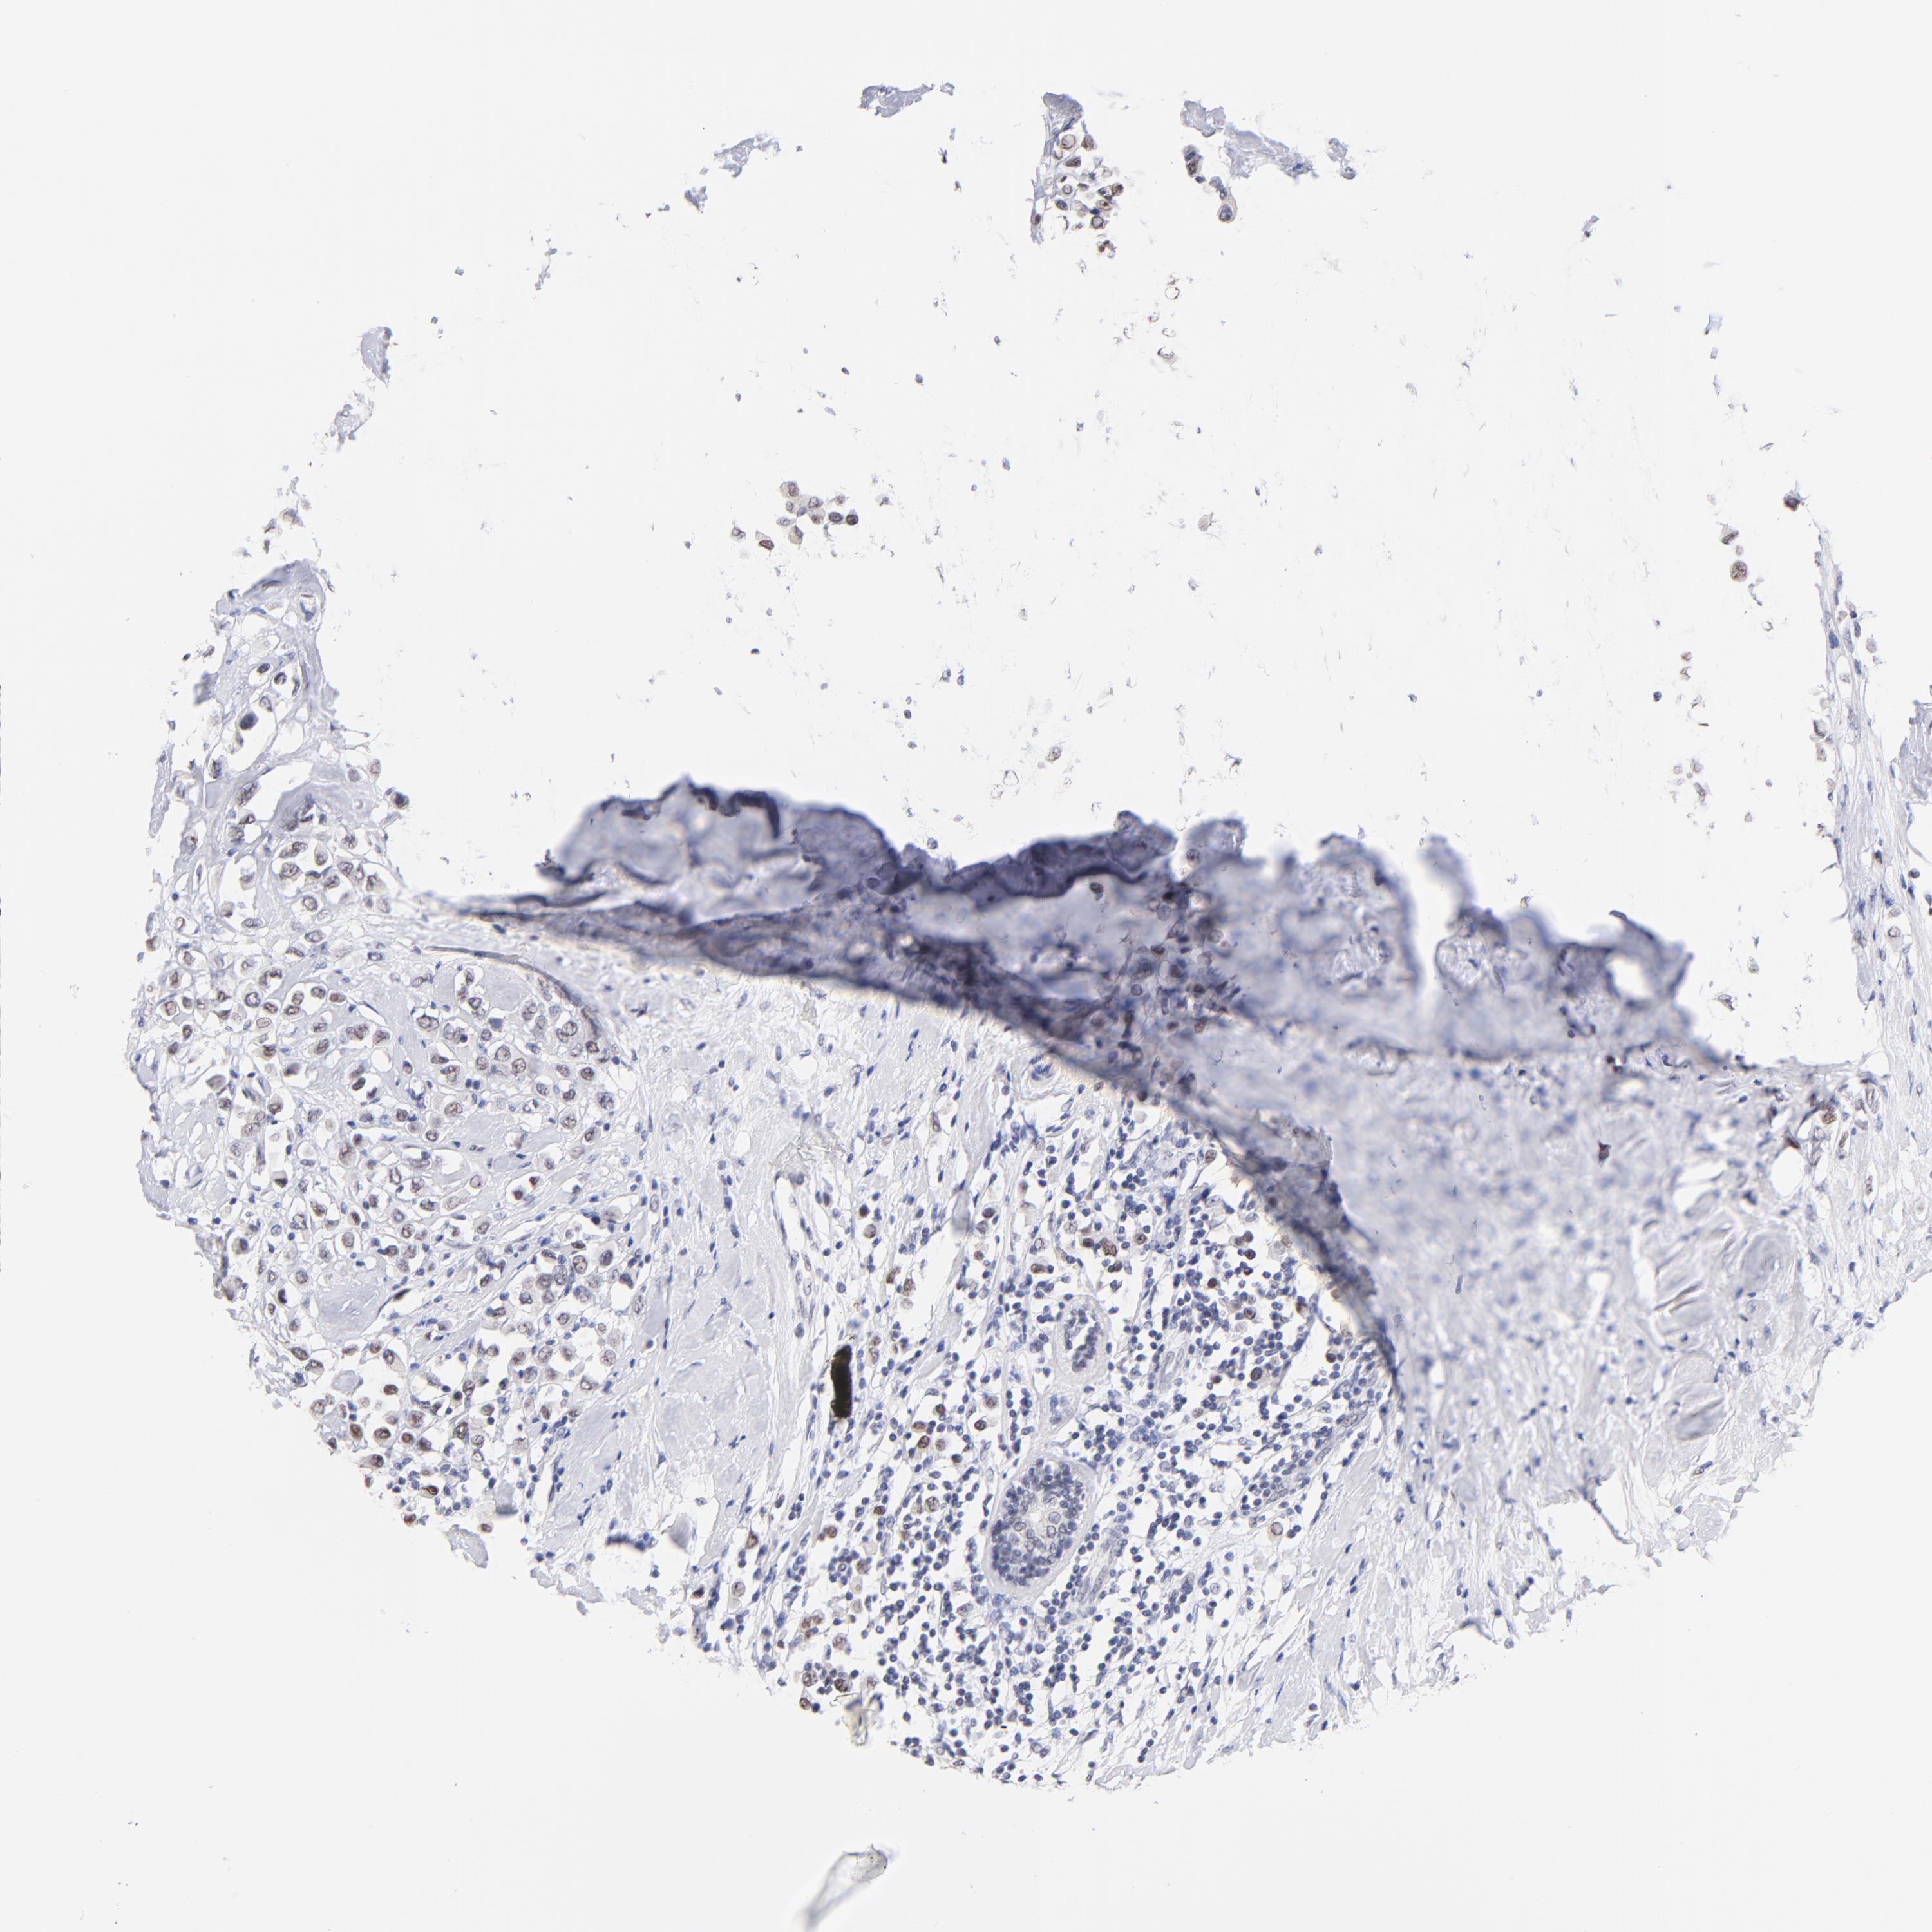

BRCA TCGA BRCA VALIDATION PROTEIN EXPRESSION

ANTIBODIES

AND

VALIDATION